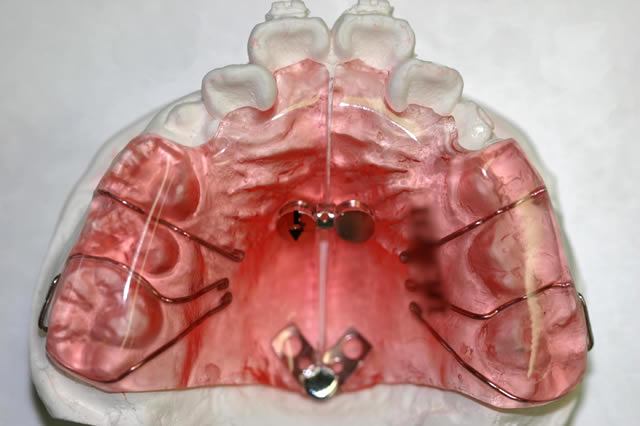

歯列の幅が狭い時に、適切なスペースを作る装置で主に歯を側方に押し広げます(広げる幅は内部のネジで調節)。患者さまによっては、永久歯に生えそろった後、第2期治療としてワイヤーを用いて全体の歯並び・咬み合せの治療を行います。